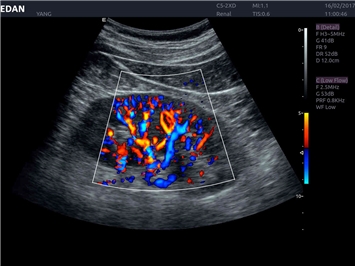

EDAN Acclarix LX4 представляет собой инновационную ультразвуковую систему, построенную на усовершенствованной платформе Acclarix. Сочетание высокого качества визуализации с интеллектуальным рабочим процессом делает эту систему оптимальным выбором для клиник, ценящих эффективность и экономичность.

Области применения:

Система Acclarix LX4 оптимально подходит для:

• Общей визуализации

• Исследования малых органов

Трехмерная реконструкция ЦДК:

Да

Энергетический допплер:

Цветовой допплер:

Color 3D: